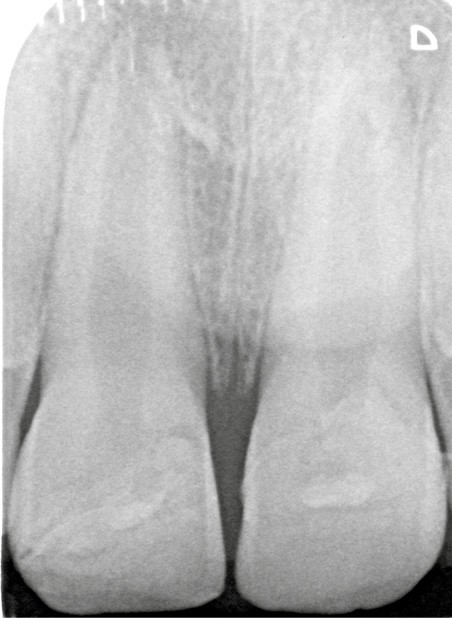

À une semaine, la radiographie (fig. 8) permet d’observer le positionnement des fragments. Les tests de sensibilité se révèlent positifs pour 11 et 21.

À 3 mois, sur la radiographie (fig. 9) l’apex semble se fermer et les tests de sensibilité sont toujours positifs. De la plaque dentaire (fig. 10) est observée. Une motivation à l’hygiène à l’aide d’un révélateur de plaque est réalisée. Par crainte, les enfants (ou les parents pour les plus jeunes) évitent fréquemment le brossage des dents traumatisées ; des gingivites peuvent être secondaires à ce défaut d’hygiène dans un contexte déjà inflammatoire consécutivement au traumatisme. Une attention particulière doit donc être portée à l’hygiène bucco-dentaire du patient.

A chaque séance, un contrôle radiographique devra être réalisé afin de vérifier l’apexogenèse de 11 et 21 et l’absence de lésion radio-claire apicale. Un test de sensibilité sera également réalisé à l’aide d’un coton froid imprégné grâce au cryospray. Les dents controlatérales seront également testées comme comparatifs des dents traumatisées.